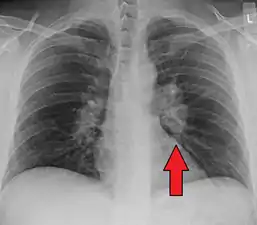

Chest radiograph changes are divided into four stages:[105]

1. bihilar lymphadenopathy

2. bihilar lymphadenopathy and reticulonodular infiltrates

3. bilateral pulmonary infiltrates

4. fibrocystic sarcoidosis typically with upward hilar retraction, cystic and bullous changes

Although people with stage 1 radiographs tend to have the acute or subacute, reversible form of the disease, those with stages 2 and 3 often have the chronic, progressive disease; these patterns do not represent consecutive "stages" of sarcoidosis. Thus, except for epidemiologic purposes, this categorization is mostly of historic interest.[28]